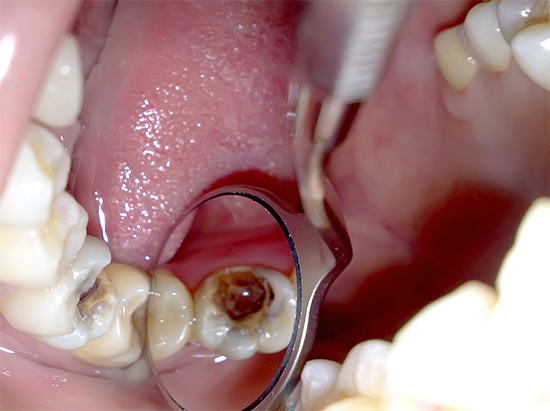

La foto sotto mostra la polpa infiammata rimossa dal dente ancor prima che subisse una fusione purulenta:

L'essudato purulento non è altro che il risultato della morte di massa di leucociti e batteri. L'accumulo di essudato inibisce il metabolismo della polpa e inizia a morire gradualmente.